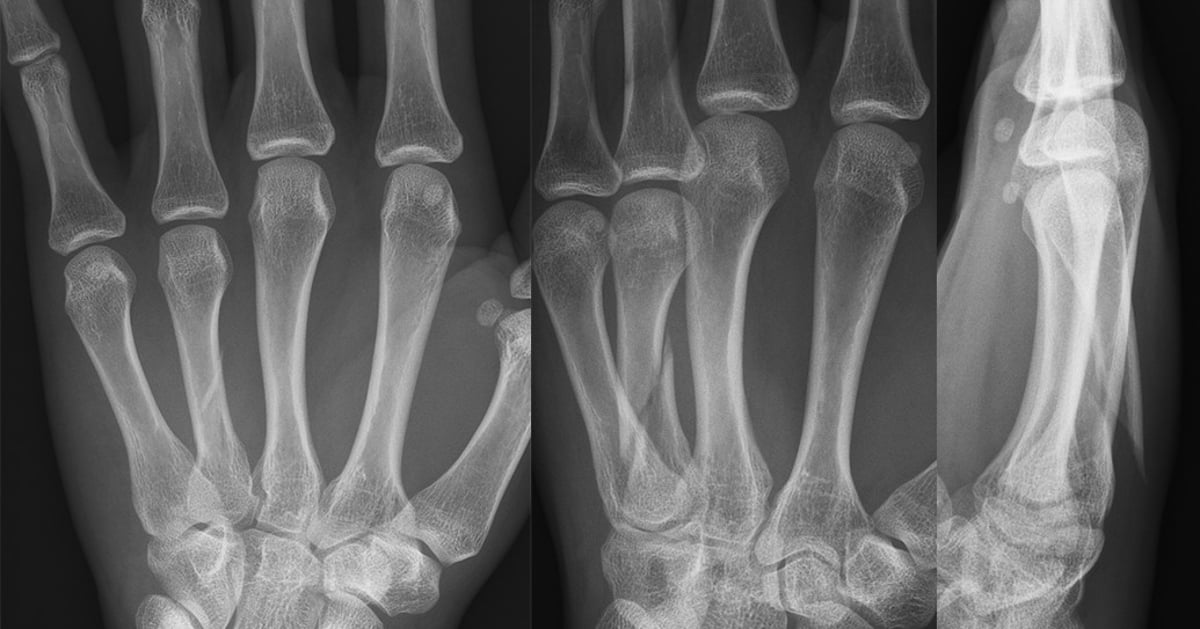

En forskningsstudie ledd från Akademiska visar att en ny behandlingsmetod för frakturer på mellanhandsbenen, fokuserad på aktiv träning, ger lika bra resultat som traditionell behandling med operation och gipsning.